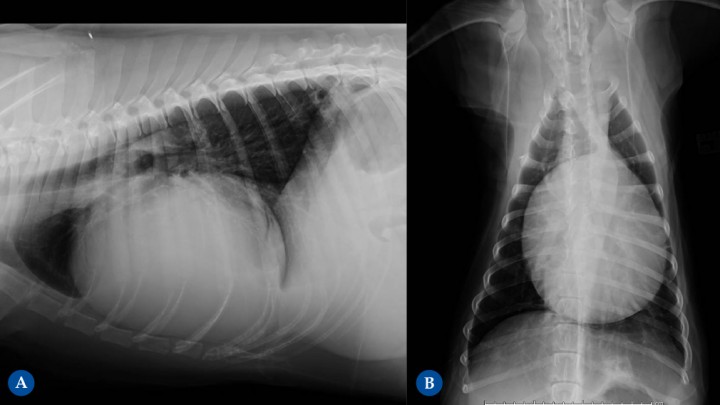

Figura 10

Golden Retriever de 10 años. Hemopericardio y pericarditis reactiva. (A) Proyección lateral derecha. (B) Proyección ventrodorsal. Diagnosticado previamente de linfoma pericárdico T atípico, en tratamiento quimioterápico. Se puede diferenciar la efusión pericárdica de la cardiomegalia en que la efusión pericárdica ocasiona un engrosamiento globoso generalizado, con bordes lisos, redondeados y muy bien definidos, sin evidenciarse un engrosamiento de una cámara cardíaca en concreto. En esta paciente se observa una silueta cardíaca que ocupa más de 2/3 del ancho de la cavidad torácica en la Fig. 10B y más de un 80% en la Fig. 10A con un mayor eje craneocaudal, ocupando 4 EIC.